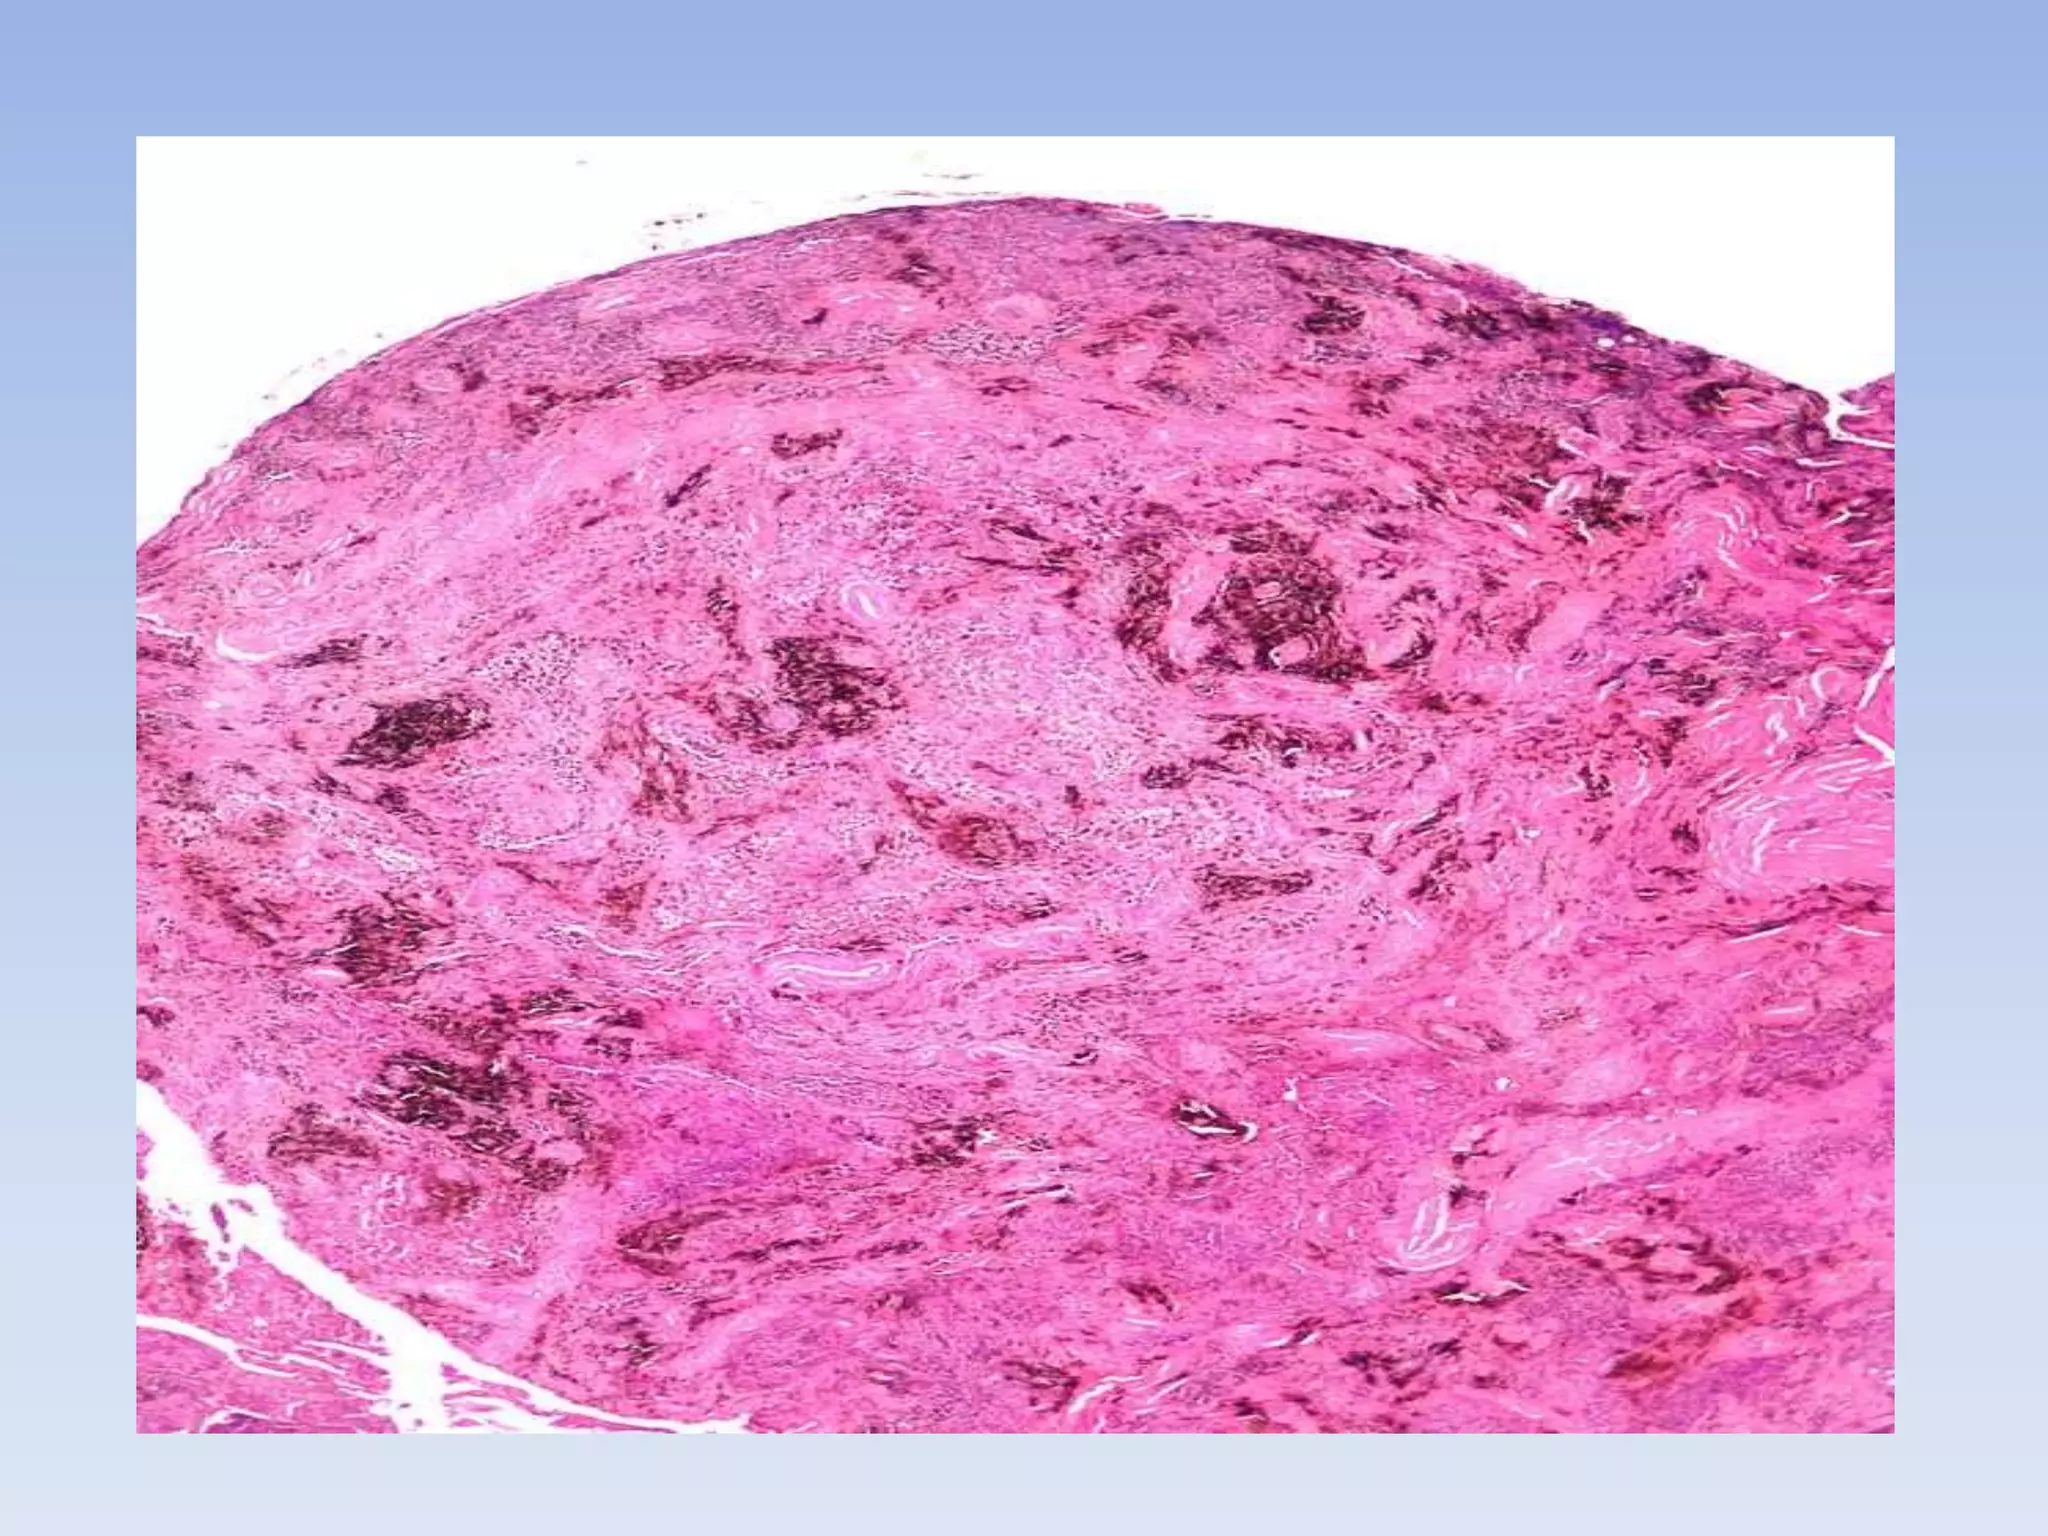

Histology

• PVNS lesions on histology demonstrate

synovial cell proliferation,

xanthomatous cell accumulation,

hemosiderin deposition, and the

presence of multinucleated giant cells

Histology • PVNSlesions on histology demonstrate synovial cell proliferation, xanthomatous cell accumulation, hemosiderin deposition, and the presence of multinucleated giant cells